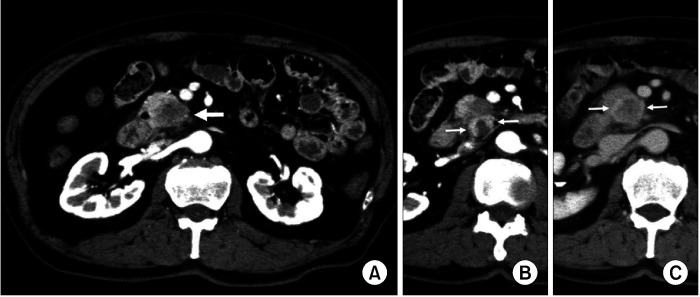

Abstract Image